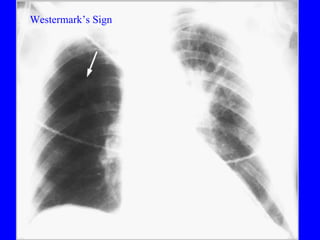

Pulmonary embolism (PE) is a common and potentially fatal condition where blood clots block arteries in the lungs. An estimated 5 million venous thromboses occur annually worldwide, with 10-30% of PE cases correctly diagnosed. Risk factors include older age, cancer, obesity, surgery, trauma, and genetic or acquired hypercoagulable states. Diagnosis involves assessing clinical probability based on symptoms and risk factors, then confirming with tests like D-dimer, chest imaging, ventilation-perfusion scanning, pulmonary angiography, or CT pulmonary angiography. Treatment focuses on anticoagulation to prevent further clotting while allowing natural lysis of existing thrombi.